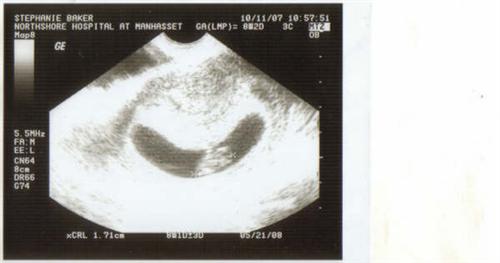

We're pregnant

8w2d